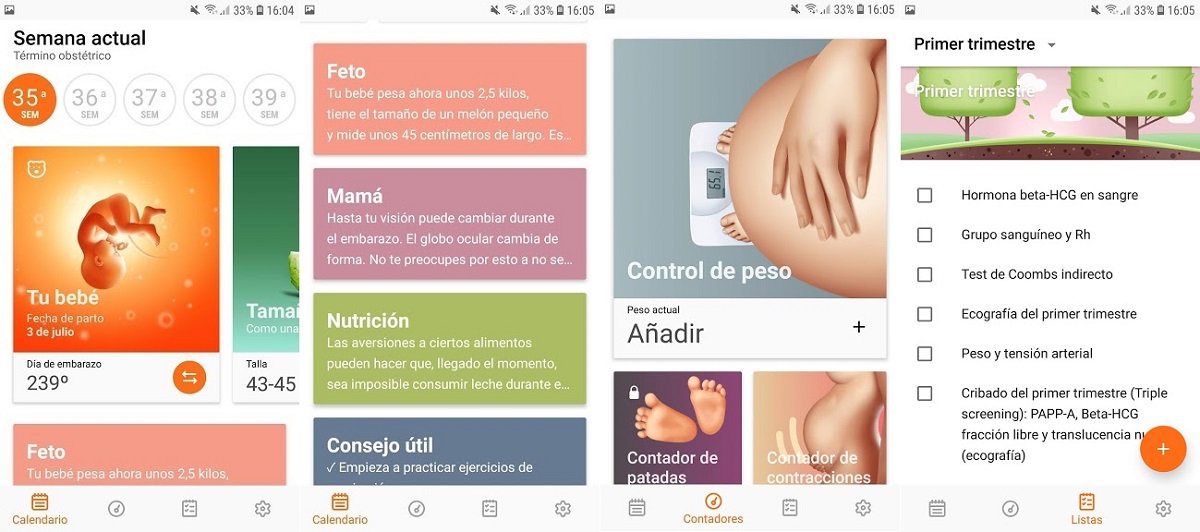

6. Embarazo día a día

Embarazo día a día es una interesante aplicación, muy bien diseñada por cierto, con la que podrás hacer un muy buen seguimiento de tu embarazo. Gráficamente es encantadora, muy clara y fácil de entender. Contiene, además de información sobre el desarrollo del pequeño, una serie de apartados para controlar diferentes parámetros: el peso, las patadas, las contracciones, la presión arterial o el crecimiento abdominal.

Nos ha gustado especialmente la sección de listas, en las que verás todo lo que necesitas para el embarazo, para antes del parto, durante y después. Podrás marcar todo aquello que ya tengas o hayas hecho